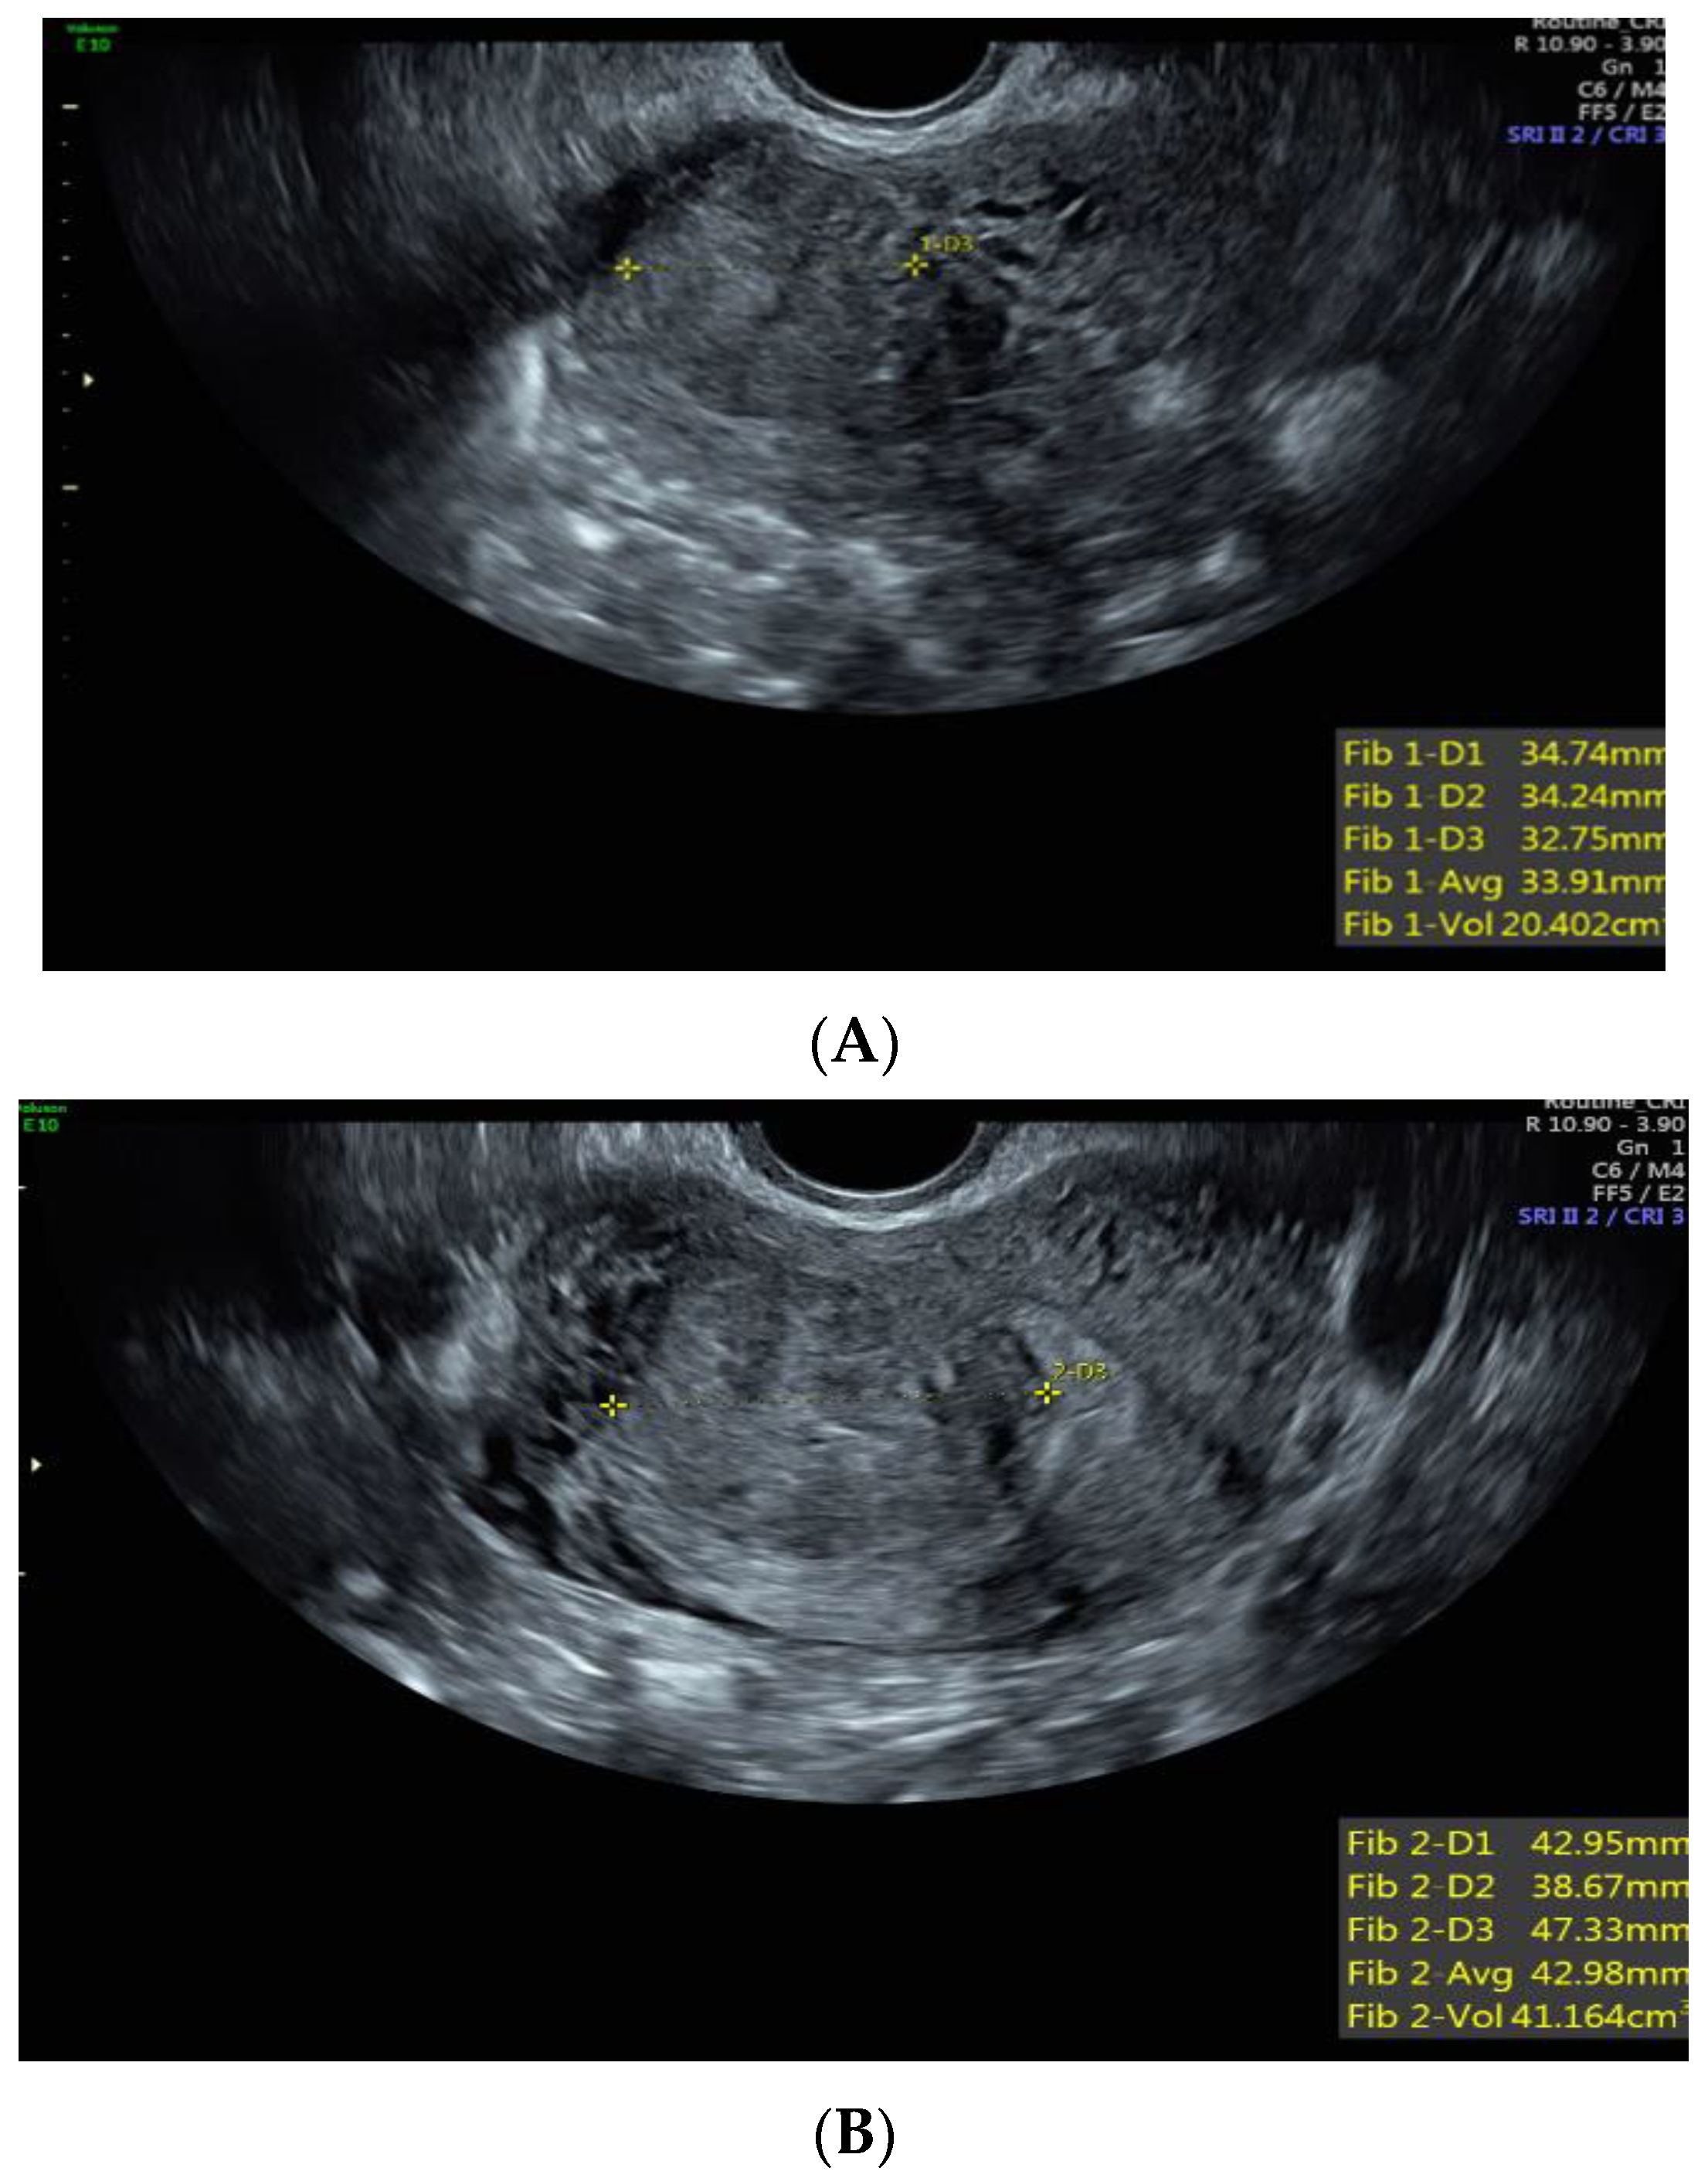

Case 1: A 37-year-old White, non-Hispanic patient presented with heavy menstrual bleeding and pelvic pain. A pelvic ultrasound revealed a 4.5 cm intramural uterine fibroid (Figure 1A) and a 3.5 cm submucosal uterine fibroid (Figure 1B). She underwent a total laparoscopic hysterectomy with bilateral salpingectomy. Pathology confirmed a leiomyoma with features of FH deficiency; germline genetic testing was negative for known pathogenic mutations.

Figure 1.

(A) Anterior intramural uterine fibroid. (B) Anterior submucous uterine fibroid.